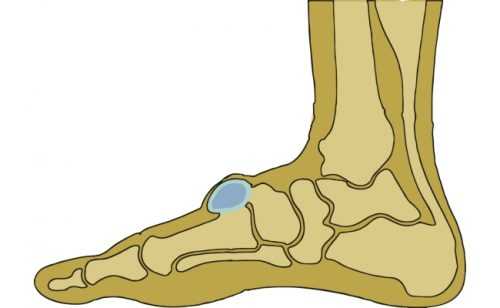

Киста стопы

Киста на стопе ноги возникает, как

правило, в пяточно-кубовидном, таранно-пяточном суставах. Причиной возникновения выступает, как правило, тендовагинит – воспаление внутренней оболочки сухожилия. По этиологии различают инфекционный и асептический тендовагинит.

Это патологический процесс, вызванный воспалением инфекционного, травматического характера, характеризуется появлением болей в области пораженного участка. При пальпации обнаруживается экспансивная опухоль с характерной крепитацией. Ткани на границе с опухолью деформируются, вызывая острые боли. Происходит распространение отека на голень, икры. Острая форма может переходить в хроническую форму, при которой характерно ограничение движений.